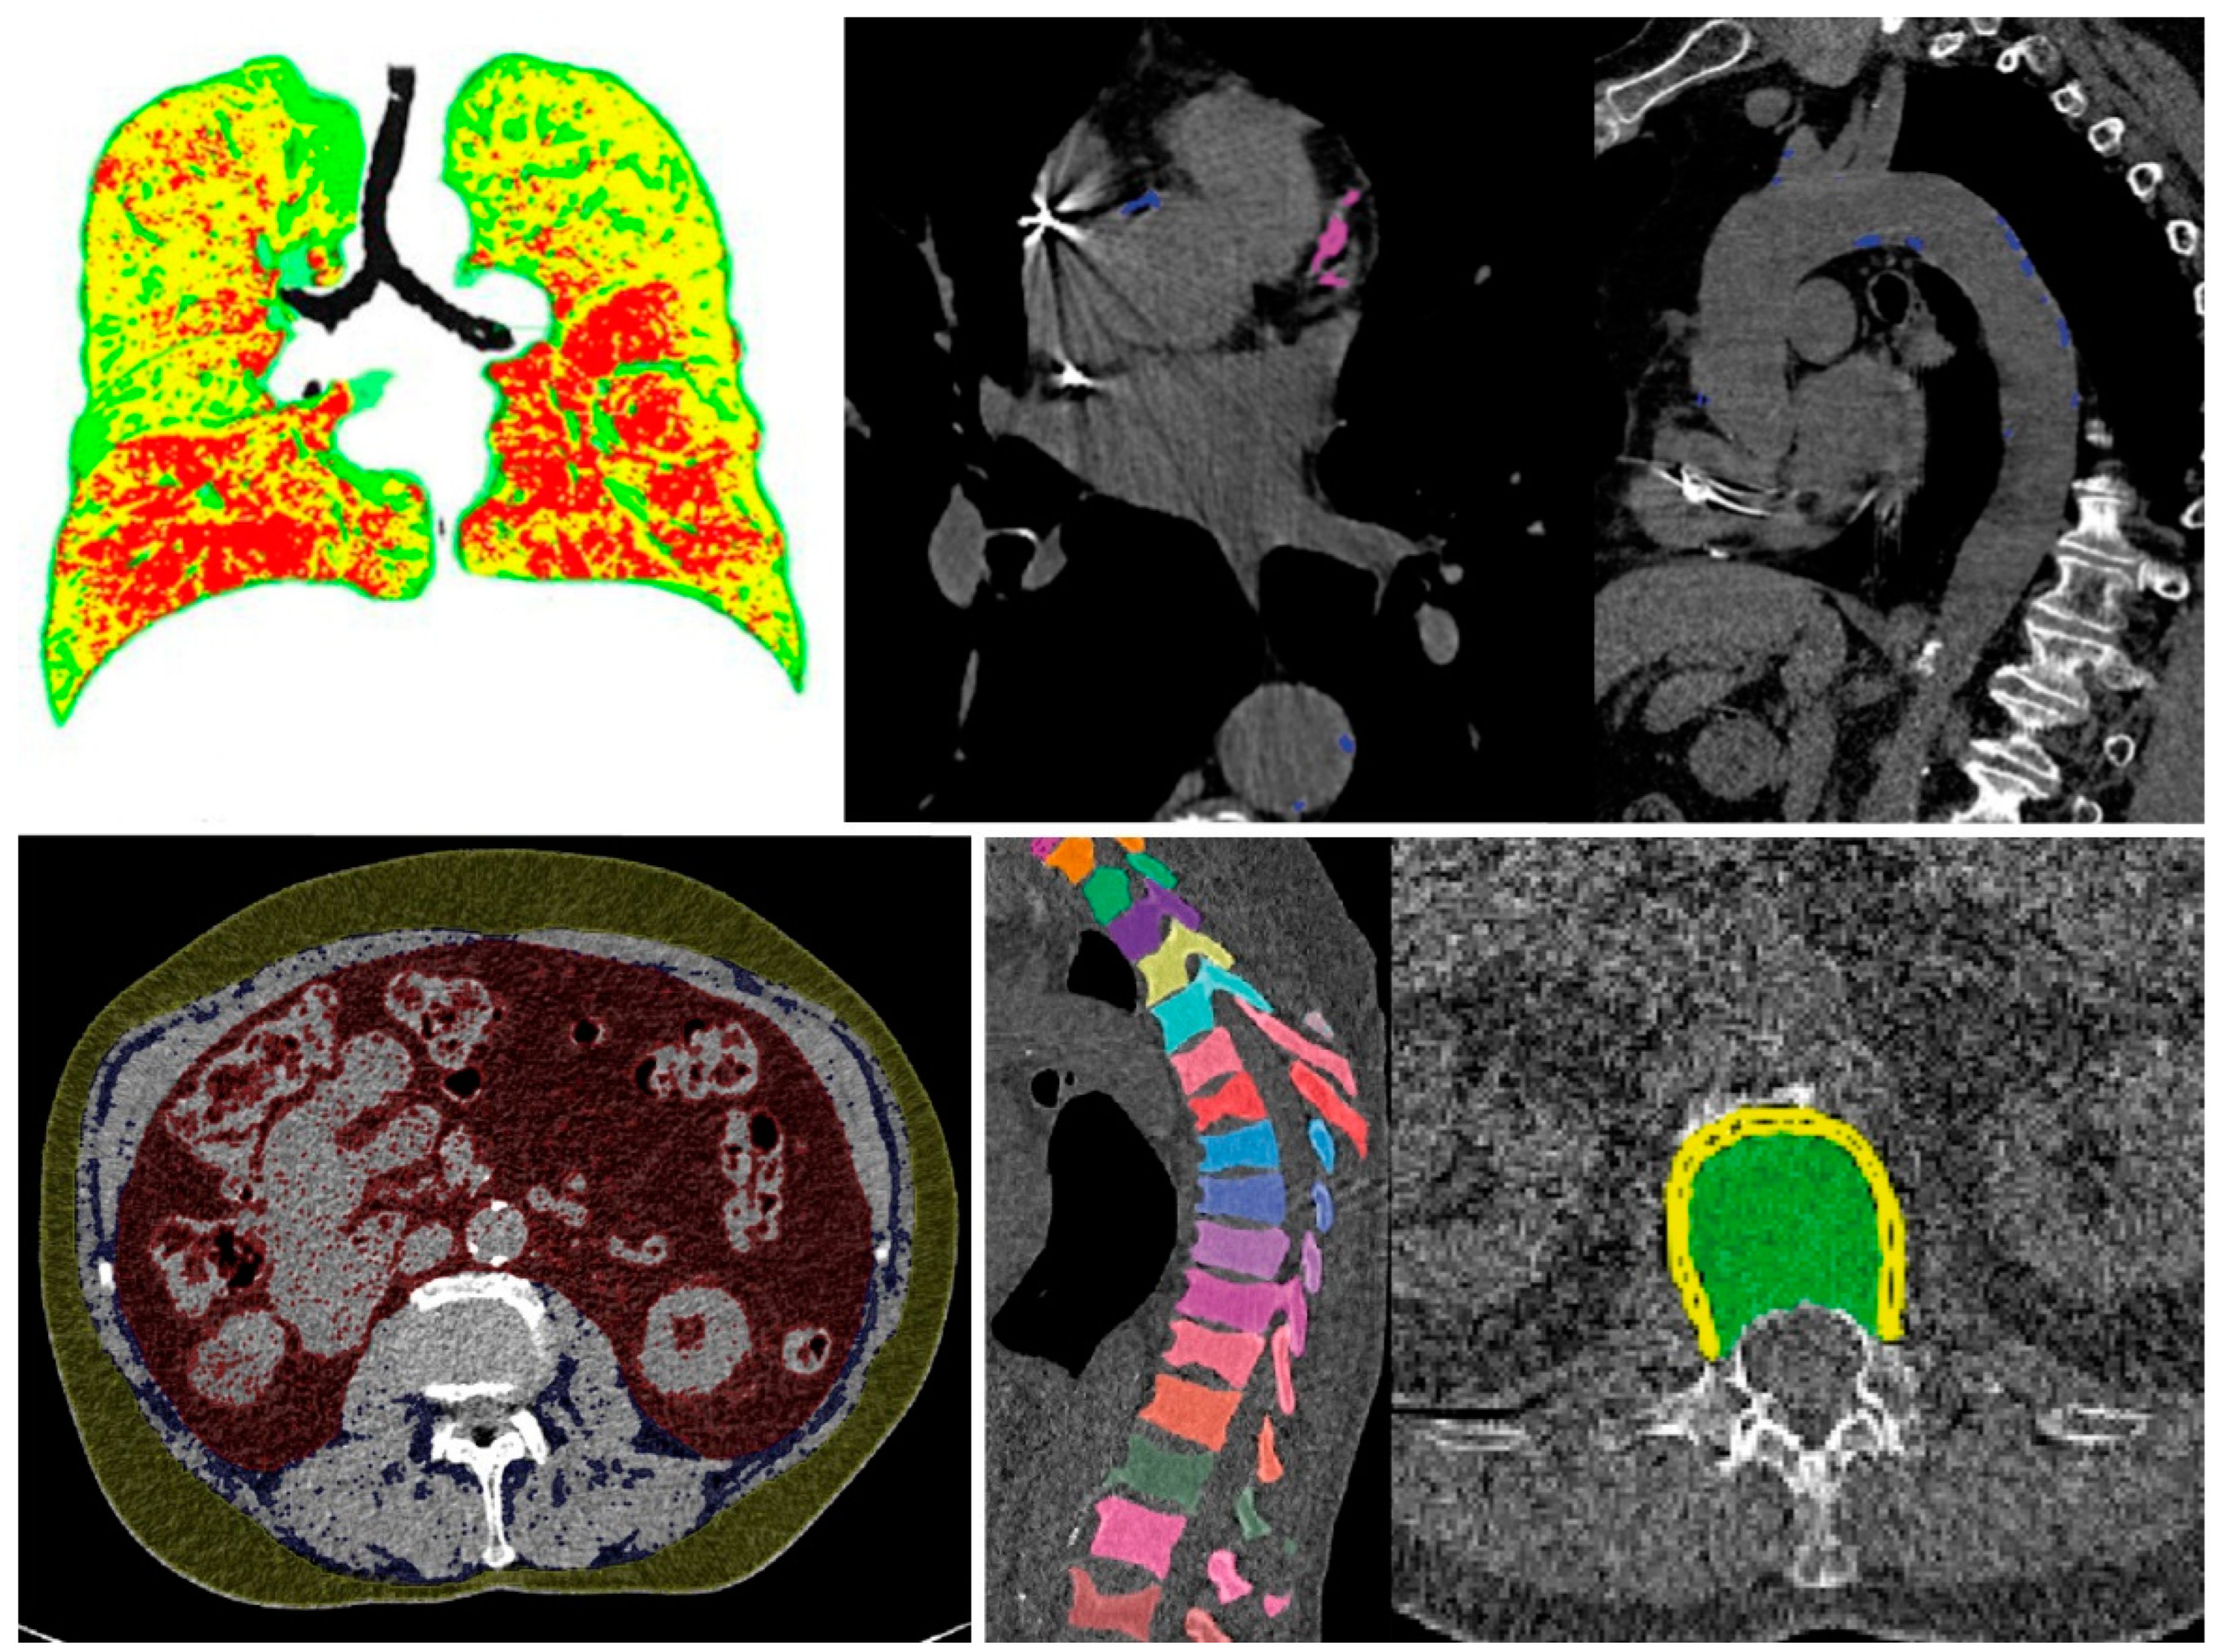

3.2.1. Example No. 1 ‘TAVI Patient’

3.2.2. Example No. 2 ‘COPD Patient’